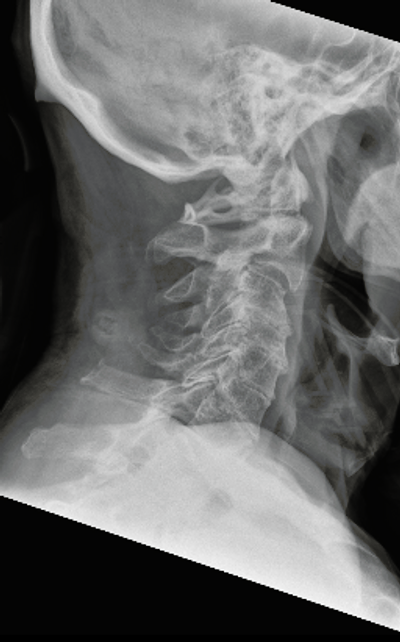

Figure 1: Lateral X-ray of an 80-year old woman with odontoid type 2 fracture, after a fall from height.